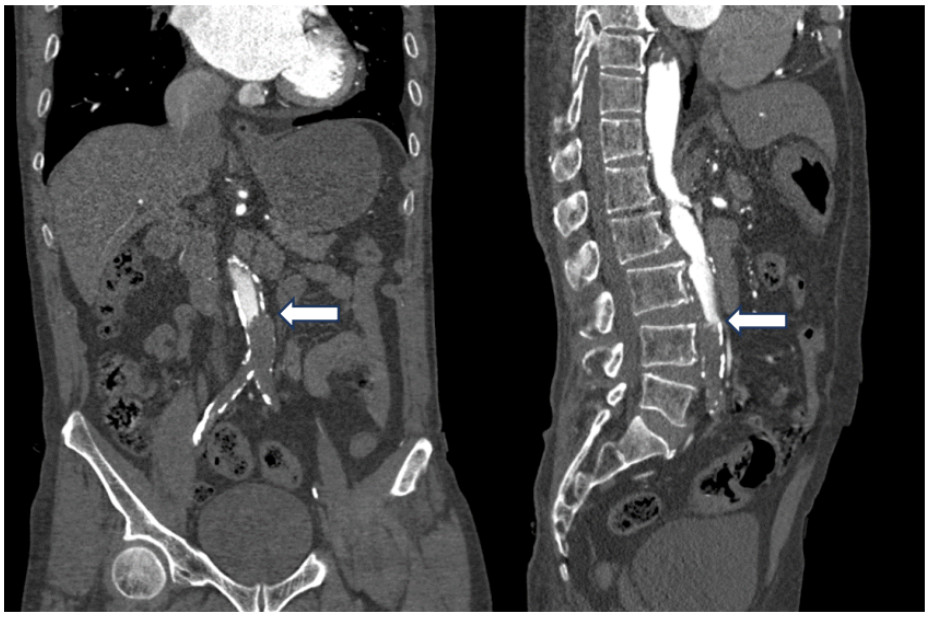

腹主动脉CTA成像示:腹主动脉近末端处-双侧髂总动脉-双髂外动脉、右髂内动脉、左髂内动脉起始部未见对比剂充盈,考虑腹主动脉急性闭塞(见图 4)。

注:A为冠状位,B为矢状位;腹主动脉远端未见对比剂充盈(箭头处) 图 4 患者主动脉CTA血管成像